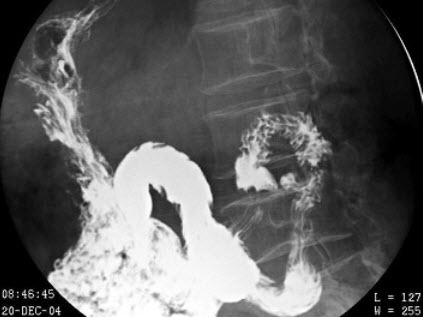

36、单项选择题

女,77岁,进行性吞咽困难月余,伴胸闷气短,腹胀。结合图像,最可能的诊断为()